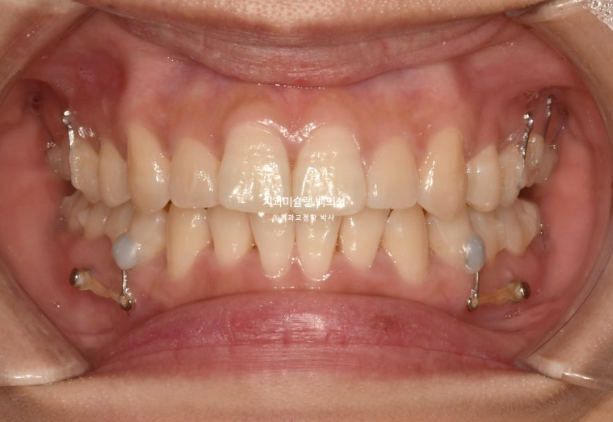

25년 5월부터 8월까지 14개 추가장치를 모두 낀 후 치료를 마무리 했습니다.

25.08

중심선은 일치하고 교합도 좋습니다.

파란화살표 둘째 큰어금니 (제2대구치)자리에 있는 치아는 사실 사랑니입니다.

그 앞 제 1대구치 자리에 와있는 치아는 사실은 제 2대구치입니다.